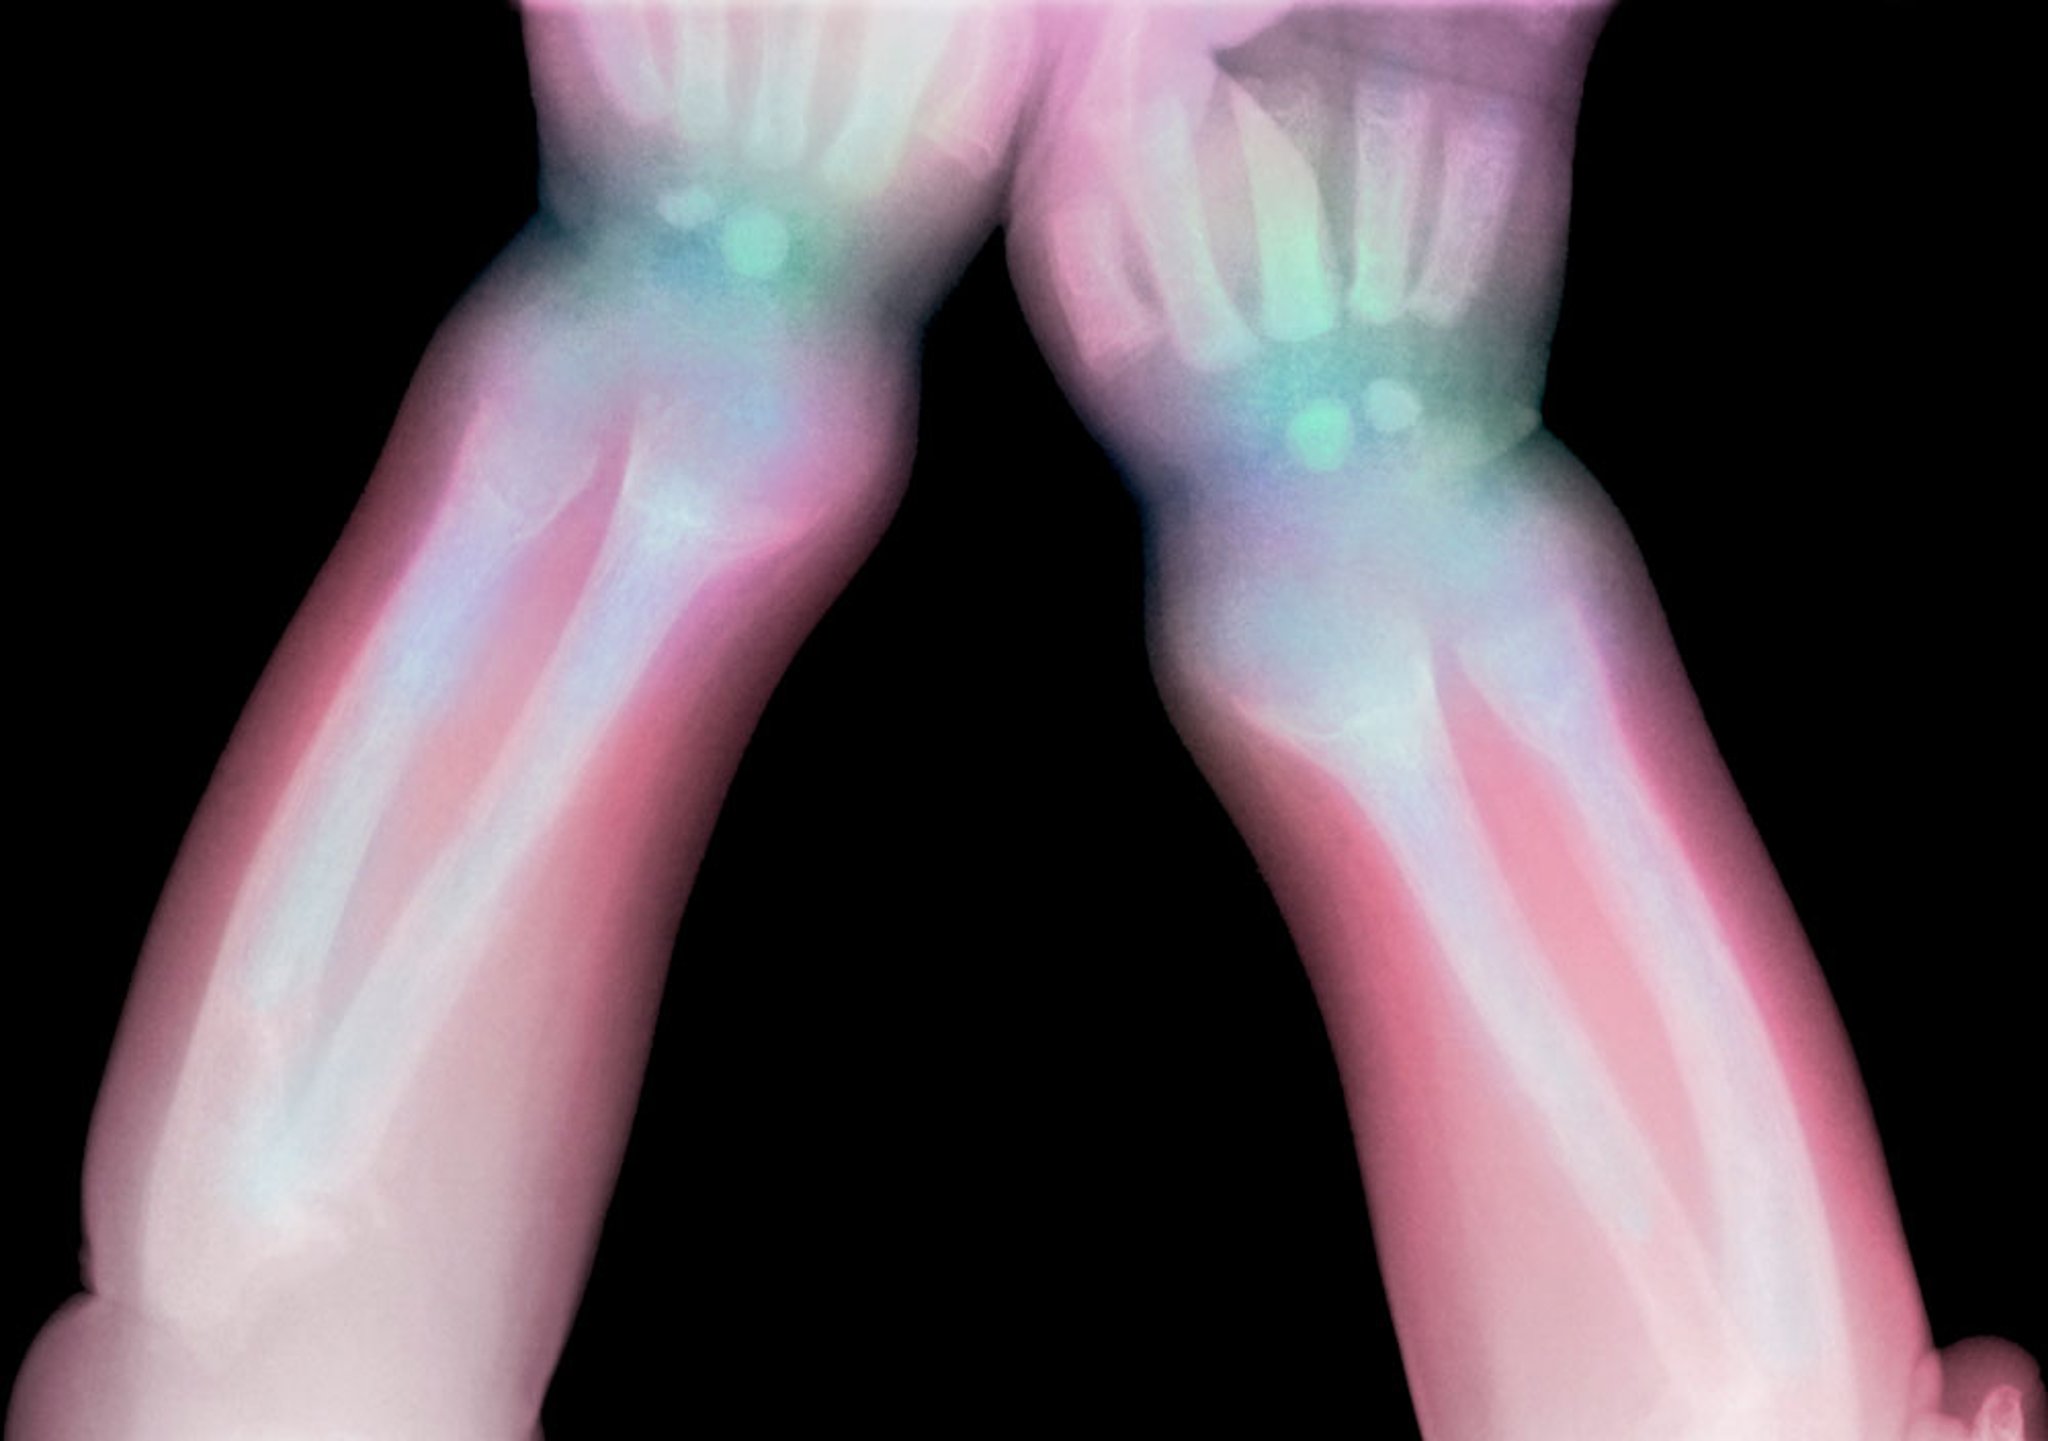

Cette radiographie montre la radiotransparence du radius et du cubitus distaux chez un enfant atteint de rachitisme.

Credit DU CANE MEDICAL IMAGING LTD / SCIENCE PHOTO LIBRARY